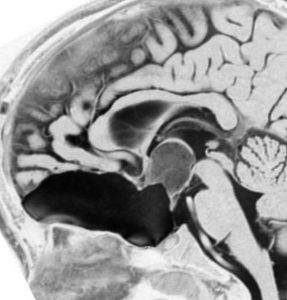

化学療法が有効なのは,上の画像のようにガドリニウム増強で強く増強されるタイプです,またT2強調画像で強い高信号になるものほど化学療法が有効です,要するに毛様粘液性星細胞腫の要素に化学療法が有効であるということです

この毛様細胞性星細胞腫はガドリニウムでほとんど増強されません(右側のMRI)から,化学療法を行っても小さくなりませんので,手術摘出する必要があります,実際に視床下部から発生したもの視交叉が犯されておらず,手術亜全摘出できました